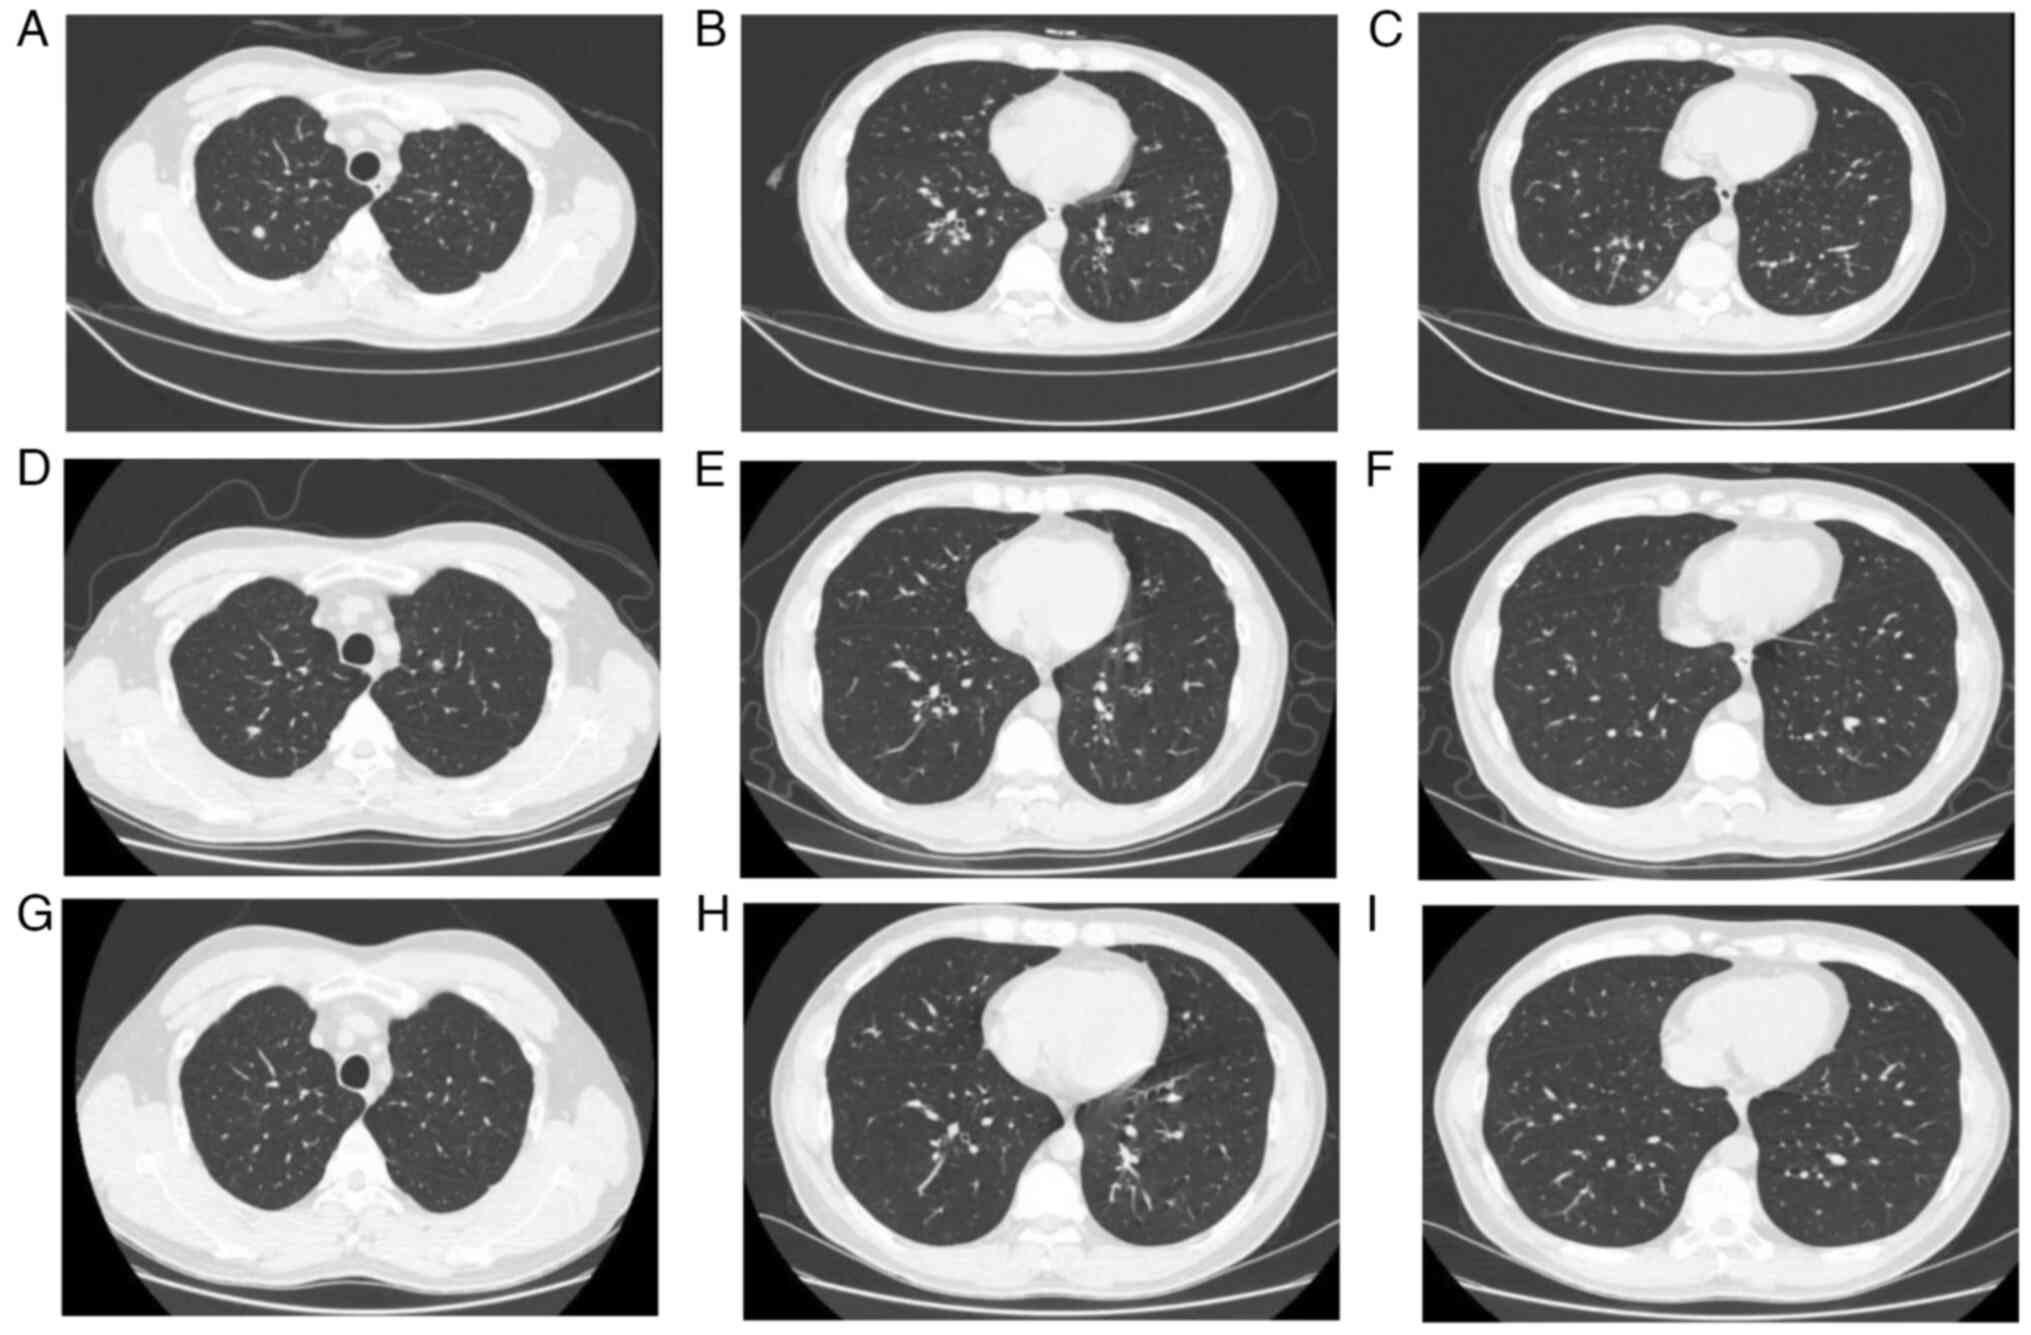

A 34-year-old female patient was admitted to the Second Affiliated Hospital of Chongqing Medical University (Chongqing, China) in January 2022, with a cough that had been worsening for >1 month and had been present for half a month. Chest CT in January 2022 (Fig. 3A-C) revealed: i) Patchy solid shadow and small perifocal speckled exudative foci in the extra-basal segment of the lower lobe of the right lung, indicating the possibility of an infectious lesion; and ii) several small nodular foci in both lungs. An electronic bronchoscopy was performed, which revealed congested and swollen bronchial tubes in all lobar segments bilaterally. The results of mNGS and other relevant laboratory tests are presented in Table II.

Figure 3

Comparison of chest CT in patient 3. (A-C) Chest CT in January 2022. (D-F) Chest CT 2 weeks later. (G-I) Chest CT in March 2022. The lesions were more clearly absorbed in March compared with at the first CT scan in January.

Therefore, the initial diagnosis was pneumonia with WD. The patient was discharged from the hospital after 7 days of anti-infective treatment with ceftriaxone (2 g qd), followed by maintenance treatment with cotrimoxazole (0.96 g BID). Subsequently, a follow-up chest CT in January 2023 (Fig. 3D-F) and March 2023 (Fig. 3G-I) showed significant improvement of the lesion.